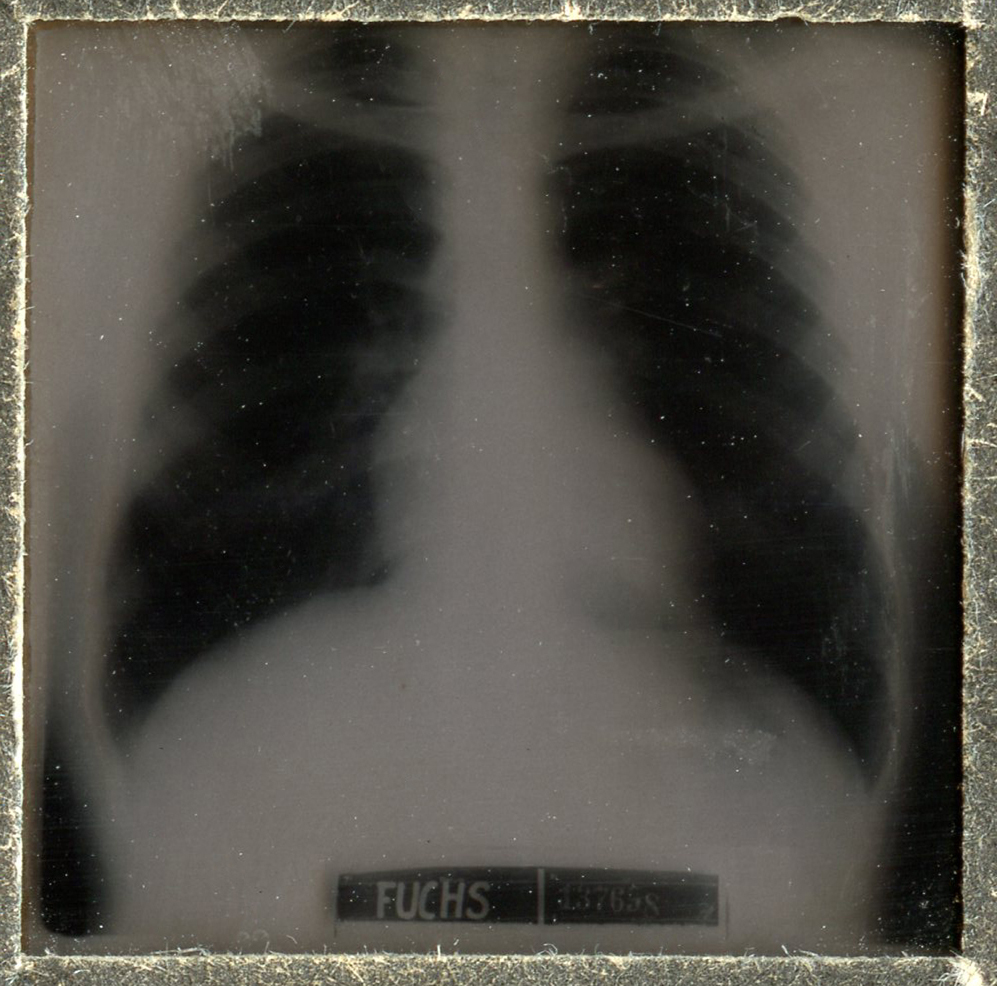

[Below: X-ray in pocket of booklet - side A. X-rays were discovered in 1895 by the German scientist Wilhelm Röntgen.]

[Below: X-ray in pocket of booklet - side B.]

[Below: X-ray close-up.]